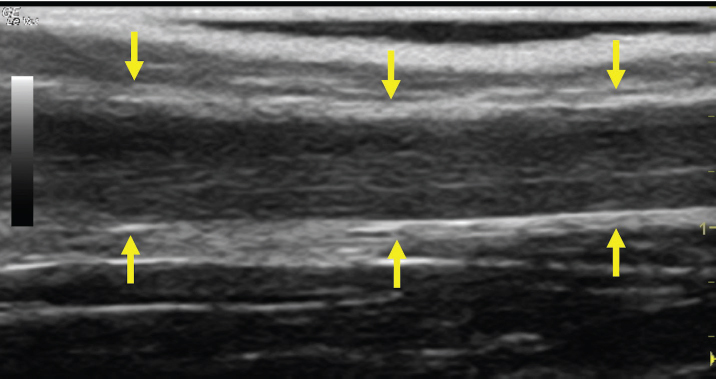

Fig. 2. A 20-G intravenous catheter placed into the right congestive facial vein in the anesthetized horse. The left jugular vein appeared as an anechoic tubular structure which collapsed under the probe pressure, the color Doppler examination revealed normal blood flow within the vessel (Fig. 3). Bi-dimensional ultrasonography of the right jugular vein showed a heterogeneous, non-cavitating, hypoechoic structure occluding a narrowed right jugular vein for about 30 cm of length localized in the proximal and mid-portion of the neck compatible with a thrombus (Fig. 4). The color Doppler examination showed blood flow through the lateral portions of the thrombus in the cranial and mid-portions of the right jugular vein (Fig. 5). Cranially to the thrombus, a marked distension of the maxillary and linguofacial veins was evident, with a turbulent and echogenic flow; the latter was compatible with blood stasis near the thrombus (Fig. 6). Caudally to the thrombus, the right jugular vein presented reduced diameter, thickened walls, and normal blood flow (Fig. 7). The cranial part of the thrombus originated from a heterogeneous scare tissue, localized at the level of the right mandibular angle (Fig. 8). After injection of the first saline contrast bolus in a right facial vein, no microbubbles appeared in the right jugular vein, caudally to the thrombus, proving the presence of a complete right jugular vein occlusion. On the contrary, after injection of the second bolus, microbubbles were visualized in the left jugular vein as small, intense, echo signals within the vein lumen, demonstrating the presence of collateral circulation that drained the blood from the right facial veins to the left jugular vein (Fig. 9). Venography results confirmed the complete occlusion of the right jugular vein and the presence of submandibular venous collaterals that connected the right facial veins with the left jugular vein (Figs. 10 and 11). Based on the previous results, the diagnosis of JVT with complete occlusion of the vessel lumen was confirmed. The horse’s owner refused any proposed medical or surgical therapy.

Fig. 4. Bi-dimensional ultrasonographic image of the right jugular vein in longitudinal section. The lumen of the vessel was occluded by a heterogeneous, non-cavitating, hypoechoic structure compatible with a thrombus (arrows).ç

Fig. 7. Bi-dimensional ultrasonographic image of the right jugular vein, caudally to the thrombus, in longitudinal section (arrows). No microbubbles appeared caudally to the thrombus, following injection of the first saline contrast bolus. DiscussionThe description of the present clinical case shows that SCU is a valid tool to assess vessel patency and presence of collateral circulation in JVT. Two-dimensional ultrasonography is useful in diagnosing JVTP and JVT and in monitoring the progression of the disease (Gardner et al., 1991; Borghesan et al., 2018). Vessel patency is usually assessed by venography and Doppler ultrasonography (Hussni et al., 2009; Borghesan et al., 2018). However, venography requires repeated x-ray exposure and Doppler ultrasonography is highly operator and equipment-dependent. Furthermore, the Doppler color examination allows evaluating blood flow presence and direction only in small portions of the vessel at a time; therefore, when the thrombus is 15–44 cm long, as happens in the JVT of horses (Borghesan et al., 2018), it does not give a global view of the obstructed vessel. On the contrary, the SCU test allows a real distinction between total and partial vessel occlusion, it can be easily performed and objectively interpreted using standard ultrasound equipment, it is not expensive and, finally, it does not require x-ray exposure.